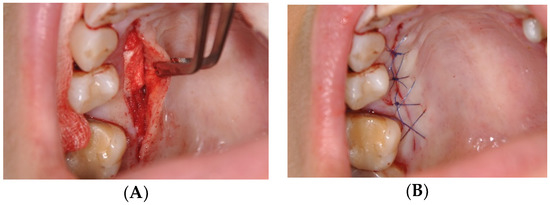

2.3. Surgical Procedures

Surgical Procedure Using Biokol®, the Xenogeneic Lyophilized Collagen Sponge